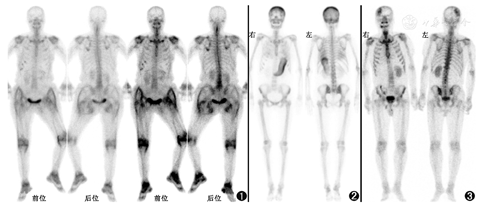

患者女,68岁,主诉右股骨颈骨折4个月,多个关节肿痛2个月。患者4个月前摔倒时右臀部着地,其后出现右髋部疼痛、右髋关节活动受限,查X线发现右股骨颈骨折,遂行右侧人工全髋关节置换术,术后病理提示骨及骨髓组织,部分骨小梁断裂,骨髓组织伴纤维化。近2个月,患者无明显诱因出现腰痛,并出现间歇性跛行,伴左膝关节、双肘关节、双手多关节肿痛。体格检查:患者跛行入室,左膝关节肿胀、压痛、屈曲畸形,双踝关节肿胀,双肘关节屈曲畸形,双指间关节肿胀、僵直。行腰椎常规MRI,见腰椎序列不稳,腰椎退行性变,L2~5椎间盘膨出,L2~S1黄韧带增厚并椎管狭窄;腰骶部皮下筋膜炎;膝关节正侧位见双侧膝关节骨质增生、骨质疏松;双手正侧位见双手及腕关节骨质疏松。为评估骨关节情况,行全身骨显像:注射99Tcm-亚甲基二膦酸盐(methylene diphosphonate, MDP)后约3 h行显像,可见全身骨骼摄取减低,四肢长骨显影不清,右下肢呈强迫体位;右侧第6~9前肋见多发点状摄取浓聚区,考虑肋骨骨折;右侧股骨颈见放射性摄取浓聚,考虑右股骨颈骨折及术后改变;双侧肩关节、腕关节、髋关节、膝关节、踝关节见放射性摄取异常增高;双侧臀部及大腿皮下、膝关节周围软组织见骨外摄取(图1)。

本例全身骨显像除骨折的表现之外,以多发外周关节、臀部及双下肢对称性皮下受累为主要表现。首先来看骨外软组织99Tcm-MDP摄取。除去药物因素和尿液污染等技术因素,骨外摄取的机制分为4类[1]:(1)转移性钙化(metastatic calcification),指高钙血症状态下钙离子在组织沉积,引起99Tcm-MDP浓聚,常见病因包括原发或继发性甲状旁腺功能亢进(图2)、肿瘤相关的骨破坏等;(2)营养不良性钙化(dystrophic calcification),指组织损伤(如外伤、缺血、细胞坏死)造成的组织内钙离子沉积,患者血钙浓度通常正常,常见病因为脑梗死(图3)、心肌梗死、镰状细胞贫血或淋巴瘤等导致的脾梗死、过度运动引起的骨骼肌损伤、术后瘢痕、皮肌炎等;(3)代谢性钙化(metabolic calcification),指由于某些代谢性因素,病变部位有局灶性的成骨活性,表现为摄取99Tcm-MDP,常见病因为骨肉瘤转移灶、外伤或炎性反应诱发的骨化性肌炎、黏液腺癌、淀粉样变(图4);(4)被隔离(sequestration),指组织对99Tcm-MDP的洗脱速度较慢,导致局部99Tcm-MDP浓度高于本底,常见病因有胸腹腔积液(图5)、静脉或淋巴梗阻、肠道淋巴管扩张、蛋白丢失性肠病。本例患者外伤及手术后出现骨外摄取,需考虑软组织损伤引起的营养不良性钙化或创伤后诱发的骨化性肌炎,但患者双下肢骨外摄取分布对称,外伤侧未见明显加重,不符合软组织损伤、骨化性肌炎导致的骨外摄取特点。结合患者高龄、多发骨折的病史,需考虑肿瘤相关骨外摄取、病理性骨折、或严重骨质疏松致骨折等。

关节病变方面,骨显像表现为对称性外周多关节受累,需考虑风湿性疾病,如类风湿关节炎。但患者年龄较大、起病较急,且进一步查血清抗核抗体、抗可溶性抗原抗体谱、人类白细胞抗原(human leucocyte antigen, HLA)-B27、类风湿因子、抗环瓜氨酸肽抗体均为阴性,不符合类风湿关节炎的表现。进一步的实验室检查提示患者贫血[Hb 100 (正常参考值范围:110~150) g/L],肾功能损伤[血肌酐(creatinine, Cr)108(正常参考值范围:45~84) μmol/L,随机尿蛋白1.0 g/L(正常:阴性)],高钙血症[血钙2.82(正常参考值范围:2.13~2.70) mmol/L],血、尿游离轻链λ(+);骨髓穿刺结果提示骨髓瘤细胞占10.5%。患者最终诊断为多发性骨髓瘤。

多发性骨髓瘤的淀粉样变多见于心脏、肾、消化道、肝、皮肤、肌肉、周围神经等(图6),少部分患者可发生淀粉样变关节病[7]。在一项系统性回顾研究中,共纳入101例诊断为多发性骨髓瘤相关淀粉样变关节病的患者(59例经关节滑膜液病理诊断),其中62.4%的患者在诊断多发性骨髓瘤前已有关节炎表现,大部分患者表现为大于4个关节的受累,易受累关节为肩关节、膝关节、手小关节[8]。有文献报道1例多发性骨髓瘤患者的全身骨显像表现为双肩关节、髋关节、膝关节、踝关节99Tcm-MDP高摄取,膝关节囊穿刺病理证实为淀粉样物质沉积,提示多发性骨髓瘤相关淀粉样变关节病患者的99Tcm-MDP全身骨显像可表现为多发外周关节受累[9],与本例表现相似。

本例患者多发性骨髓瘤诊断明确,是否合并关节周围及皮下软组织淀粉样变、骨髓瘤累及范围还有待进一步评估。全身骨显像除显示骨骼病变外,异常的关节病变及骨外摄取对鉴别诊断及疾病的评估也具有重要意义。